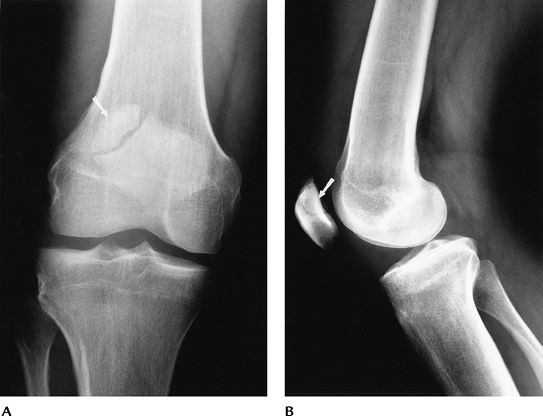

Skeletal Trauma: Osteochondral Fractures

Key Facts

Fractures involving the joint surface result from direct blows or shearing forces.

Fractures may be subtle, requiring CT or MRI for detection.

Osteochondral patellar fractures are commonly associated with dislocation.

Associated soft tissue injury is common.

P.212

![]() |

FIGURE 5-1

Patellar view demonstrating subluxation after reduction of a patellar dislocation. There is a displaced osteochondral fragment (arrow) laterally. |

Suggested Reading

Capps GW, Hayes CW. Easily missed injuries about the knee. Radiographics 1994;14:1191–1210.

Dezell PB, Schils JP, Recht MP. Subtle fractures about the knee: Innocuous appearing yet indicative of internal derangement. AJR Am J Roentgenol 1996;167:699–703.